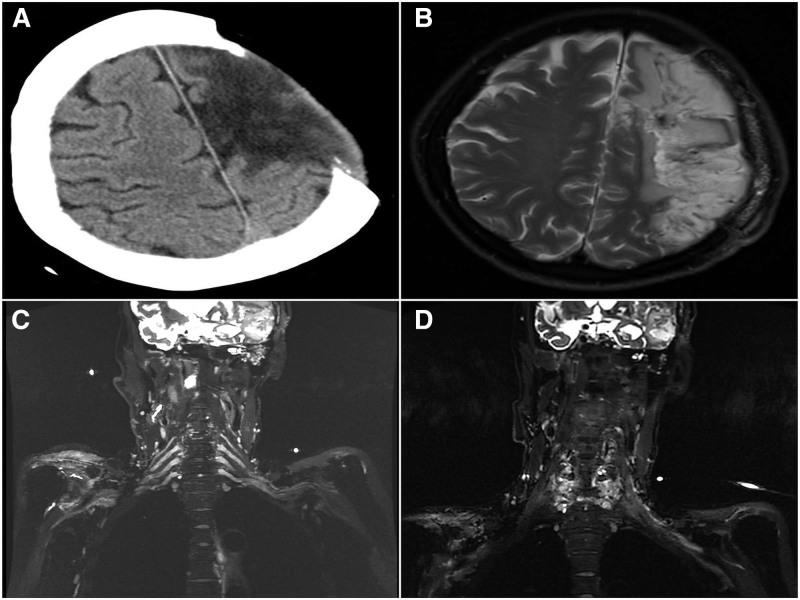

Several surgical approaches for contralateral C7 (CC7) nerve root transfer (NRT) exist, but they come with challenges such as long nerve bridging distances, complex surgical anatomy, and prolonged recovery times. Our objective was to evaluate and compare the clinical efficacy and safety of the posterior single-incision CC7 (PSCC7) NRT approach (posterior group) with the traditional anterior CC7 (ACC7) NRT approach (anterior group) for treating post-stroke upper limb spastic hemiplegia (PULSH). In this retrospective study, we retrieved and compared clinical efficacy as well as safety of the posterior group with the traditional anterior group for treating PULSH between February 2024 and February 2025. Key outcome measures included operative time, intraoperative blood loss, postoperative complications, and functional recovery at 6-month follow-up. In all, 12 patients who underwent the posterior group and 30 patients (control group) who underwent the traditional anterior group were retrieved from the hospital records. The posterior group demonstrated significantly shorter operative times (3.2 ± 0.5 hours vs 4.5 ± 0.8 hours, P < .01) and less intraoperative blood loss (150 ± 4 0 mL vs 280 ± 70 mL, P < .01) compared to the anterior group. The posterior group achieved comparable or superior improvements in Modified Ashworth Scale scores (1.2 ± 0.3 vs 1.5 ± 0.4, P > .05) and Berg Balance Scale scores (42 ± 5 vs 39 ± 6, P > .05). The posterior group is a safe and effective treatment for PULSH. It offers the advantages of reduced surgical trauma and shorter operative time.